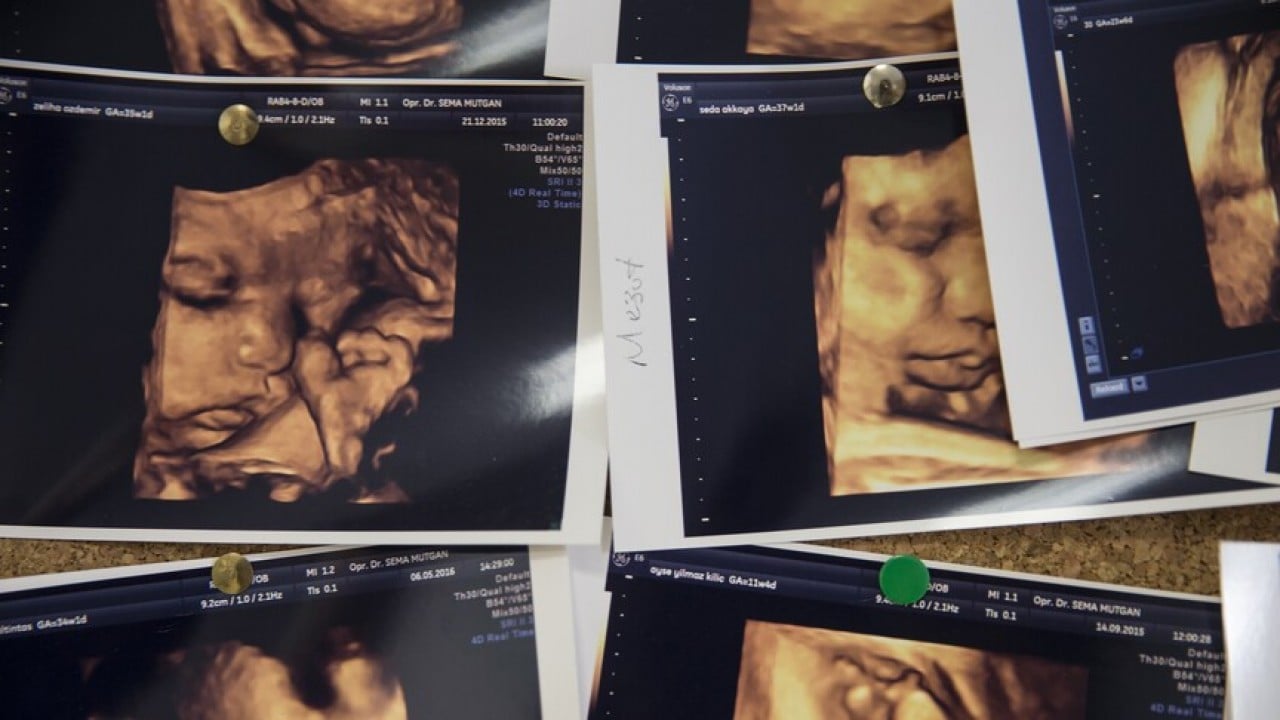

Türkiye Hemofili Derneği Başkanı ve İstanbul Üniversitesi Rektörü Prof. Dr. Bülent Zülfikar, annenin gençliğinde oluşan mutasyonun bebeğinde hemofiliye yol açabildiğini belirterek, tedavi edilmeyen hastalığın kalıcı hasarlara neden olabileceğini söyledi.

Yenidoğanlarda erken tanı ile tedavi sürecinin daha kolay olacağını vurgulayan Zülfikar, "Vakaların yüzde 60-65'inin ailesinde bu hastalık varsa çocuklarda da olabiliyor. Annenin hamileliğinde veya genç kızlığında bir mutasyon olup, gen değişikliği olmuşsa çocuğunda bu hastalık ortaya çıkıyor. Yani bebek bu hastalıkla doğuyor." dedi.